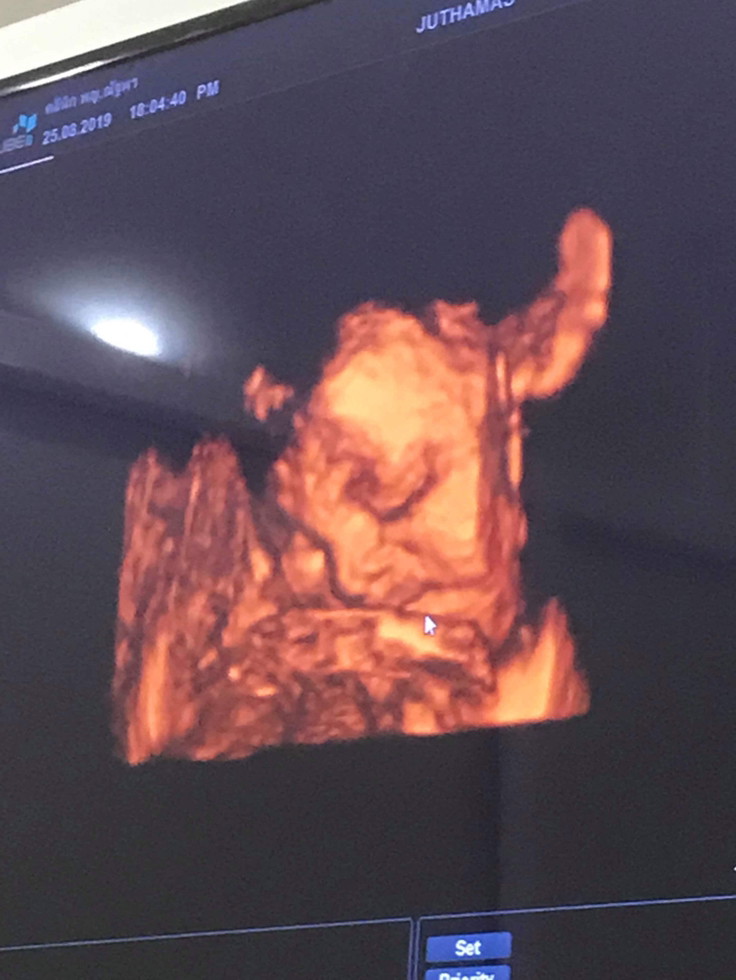

มีโพสต์ท่าเท้าคางด้วยนะลูก ไม่ธรรมดาเลยนะ 😁

หลับอยู่นะแม่ ให้หมอมากวนผมทำไม 😂🤗